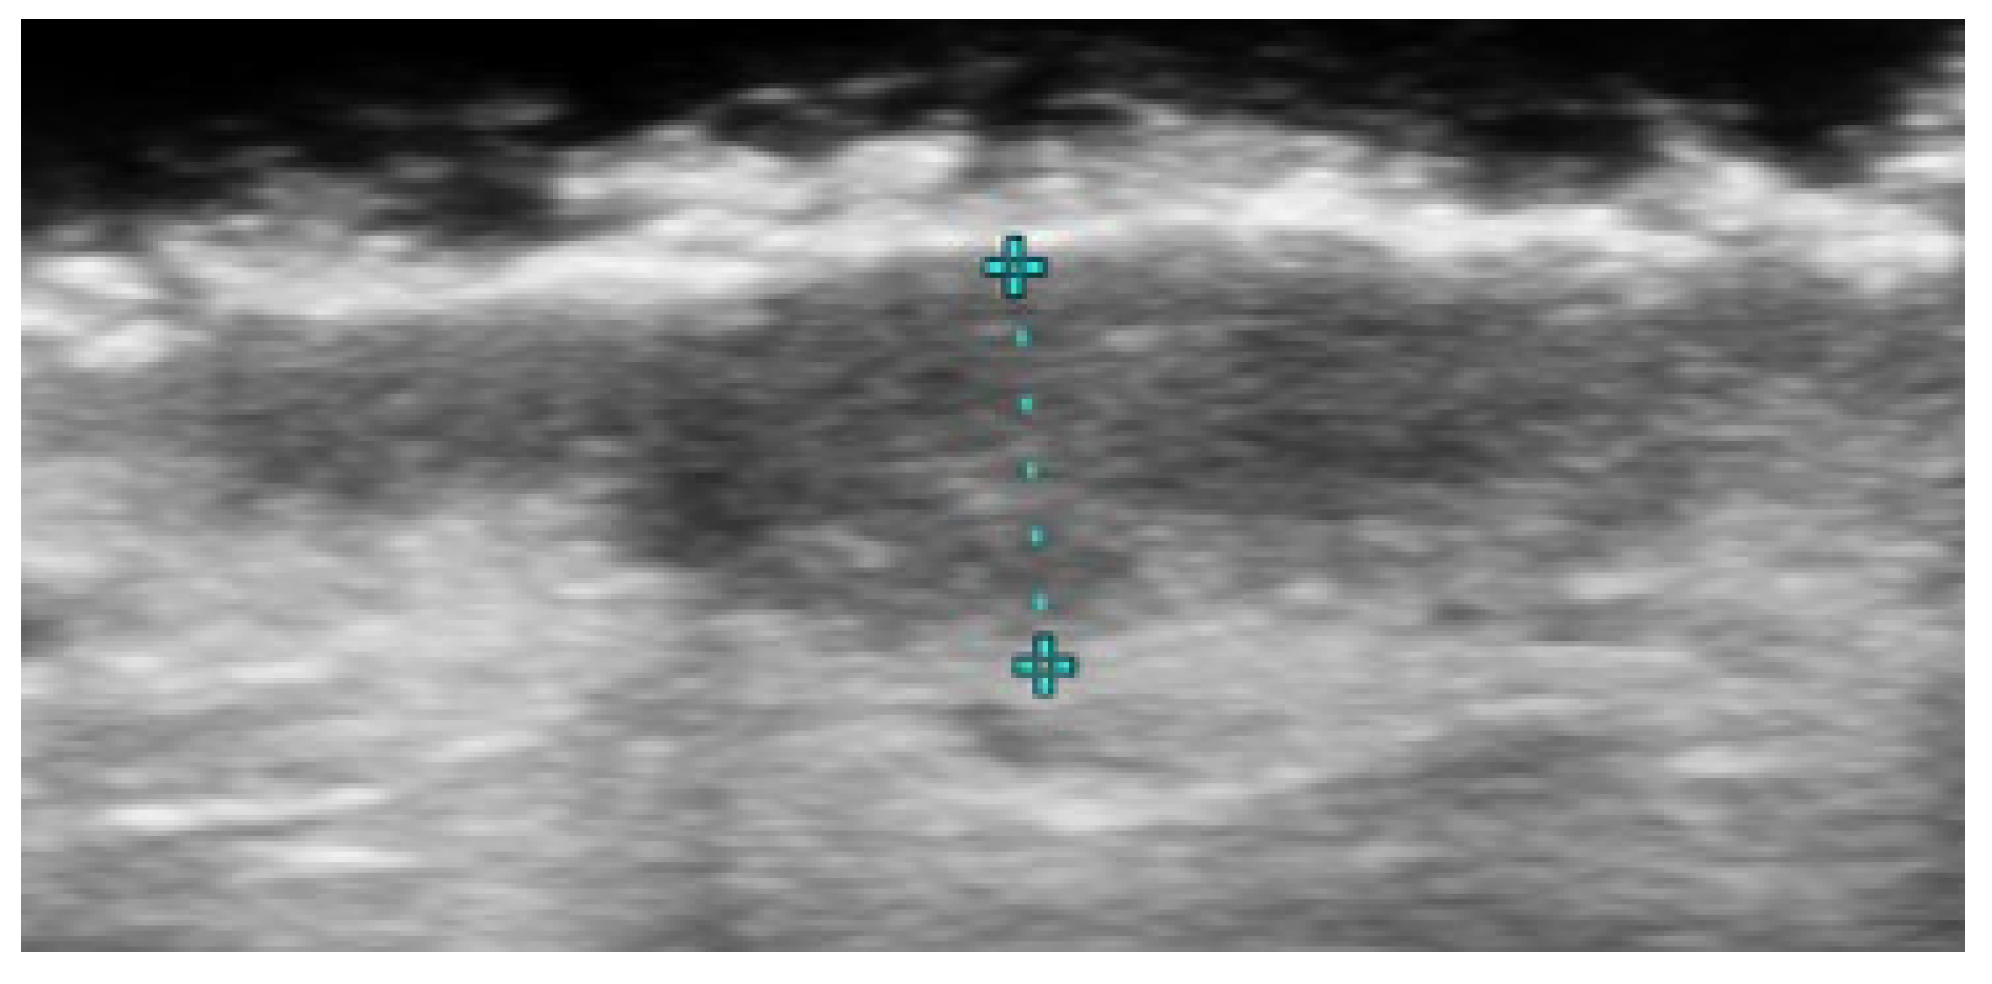

- Michelucci, A.; Dini, V.; Salvia, G.; Granieri, G.; Manzo Margiotta, F.; Panduri, S.; Morganti, R.; Romanelli, M. Assessment and Monitoring of Nail Psoriasis with Ultra-High Frequency Ultrasound: Preliminary Results. Diagnostics 2023, 13, 2716. [Google Scholar] [CrossRef]